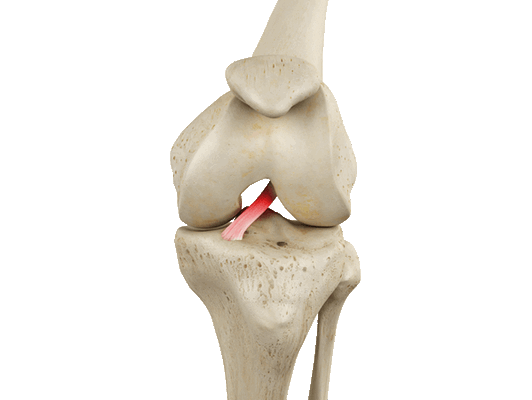

Артроскопическая пластика передней крестообразной связки коленного сустава - это один из методов лечения разрывов и повреждений крестообразной связки. Крепление связки производят фиксаторами, которые со временем рассасываются в кости и не оставляют следов в кости.

Артроскопическая пластика передней крестообразной связки коленного сустава

· первым этапом выполняется диагностическая артроскопия сустава, устанавливается характер поражения связок, сопутствующие проблемы с менисками, хрящом. При реконструкции передней крестообразной связки выполняется замещение поврежденной связки аутотрансплантатом. Для этого при помощи кусачек, артрошейвера (расходный материал - лезвие шейвера), артроскопического электрода (расходный материал - электрод) производится вапоризация и удаляются остатки поврежденной связки;

· при помощи специального инструмента в области «гусиной лапки» выполняется забор аутотрансплантатов сухожилий подколенных мышц (полусухожильная и нежная), по специальной технике формируется аутотрансплантат ПКС (расходный материал - полиэтиленовая плетеная нить - 2 шт.). Либо соответствующим способом производится забор другого вида аутотрансплантата (из сухожилия прямой мышцы бедра с или без костного блока, из связки надколенника с костными блоками) с формированием из них аутотрансплантата. Либо используется синтетический или аллотрансплантат;

· далее в соответствие с диаметром аутотрансплантата в бедренной и большеберцовой костях формируются каналы, в которые заводится аутотрансплантат. Формирование каналов выполняется при помощи специальных направителей бедренный и тибиальный таким образом, чтобы повторить геометрию нативной ПКС. В латеральном мыщелке бедренной кости формирование канала выполняется по спице диаметром 4 мм (расходный материал), при этом проведение направляющей спицы предпочтительно через антеромедиальный доступ, в большеберцовой кости по спице диаметром 2,4 мм (расходный материал). Подготовленный аутотрансплантат через тоннель большеберцовой кости заводится в тоннель бедренной кости. Фиксация на бедре кортикальная при помощи металлического или биологического фиксатора за мыщелок бедра (расходный материал) или иным фиксатором или способом (другие виды экстракортикального, внутриканального фиксатора), в тоннеле большеберцовой кости фиксация выполняется при помощи биокомпозитного винта (расходный материал) или иным фиксатором или способом (другие виды экстракортикального, внутриканального фиксатора).

Передняя крестообразная связка отвечает за динамическую устойчивость коленного сустава, фиксируя голень от нефизиологического смещения кпереди и поддерживая наружный мыщелок большой берцовой кости. Более 1/2 стабильности коленного отдела обеспечивается благодаря ПКС. Именно поэтому данную структуру специалисты называют первым стабилизатором колена, без нее сустав нормально работать не сможет. Располагается она в самом центре костного соединения, перекрещиваясь с задней крестообразной связкой х-образно, что и дало этим двум структурным элементам одноименные названия. Мы же будем говорить сейчас конкретно о ПКС и посттравматической реконструктивно-пластической ее коррекции.

Операция на ПКС: виды пластики, принцип выполнения

Любая пластическая процедура на ПКС в настоящий момент выполняется методом малоинвазивной артроскопии. Артроскопический сеанс проходит закрытым способом под спинномозговой анестезией. Операция относится к щадящему типу хирургии высокой точности, поэтому мягким тканям, нервным и сосудистым образованиям не причиняется ущерб. Кроме того, манипуляции проводятся сугубо на пострадавшем участке, а после вмешательства никаких рубцов и шрамов не остается.

Чтобы осуществить реконструкцию поврежденного элемента, достаточно сделать один 5-мм прокол для оптического зонда, в который встроена миниатюрная видеокамера, и 1-2 дополнительных доступа (не более 8 мм в диаметре). Через вспомогательные отверстия хирург микрохирургическими инструментами будет заниматься воссозданием испорченной области. Зрительный контроль обеспечивает артроскоп (эндоскопический зонд), который выводит изображение оперируемой зоны на монитор в 40-60-кратном увеличении. Оперативное вмешательство может быть выполнено несколькими способами, рассмотрим их дальше.

Аутотрансплантация

В данном случае пересаживается фрагмент сухожилий пациента, взятый из мышц бедра, иногда берут материал из связок или сухожилий надколенника. На функциональности донорского участка это никак не отражается. Техника выполнения реконструкции заключается в удалении разорванных связочных структур с последующим внедрением на их место подготовленного трансплантата из сухожилий.

Зона «забора» материала.

Концевые участки сухожильного лоскута вдеваются в просверленные каналы бедренной и большеберцовой кости и натягиваются до нужных параметров, после чего закрепляются биоразлагаемыми винтами либо садятся на специальные петли. Через несколько месяцев без проблем происходит их полное врастание в кость. Методика хорошо изучена и имеет внушительную доказательную базу эффективности, поэтому является на сегодняшний день самой применяемой тактикой лечения ПКС, «золотым стандартом» ортопедии и травматологии.